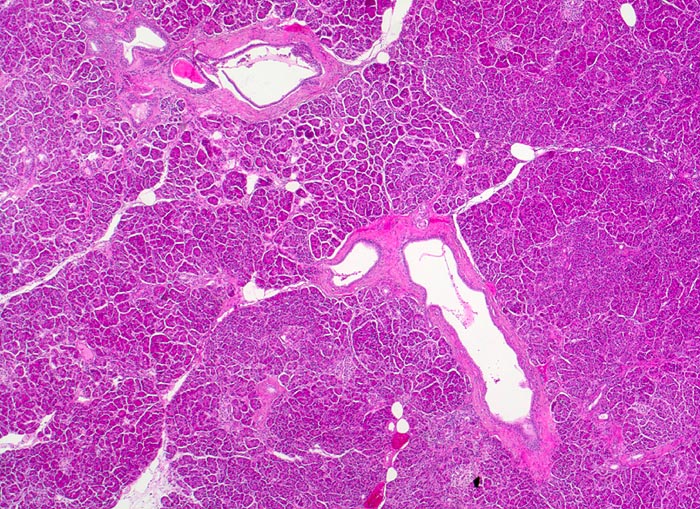

Die meisten Pankreaskarzinome sind mässig bis hoch differenziert und führen zu einer deutlichen desmoplastischen Stromareaktion (derbe Konsistenz). Hochdifferenzierte Tumoren (> 1502) können sehr ähnlich aussehen wie eine chronische Pankreatitis (> 4243). Im Gegensatz zur Pankreatitis sind die neoplastischen Drüsen verformt oder rupturiert und zeigen zelluläre Atypien (grosse polymorphe Kerne mit prominenten Nucleolen). Die Tumordrüsen sind unregelmässig im Stroma angeordnet und nicht lobulär wie in der Pankreatitis. Nicht selten ist eine Nervenscheideninvasion nachweisbar (> 5884). Gelegentlich zeigen die Gänge im tumorfreien Parenchym dysplastische Veränderungen oder der Tumor breitet sich intraduktal entlang des Pankreasganges aus.

• Rechts oben Reste von nicht neoplastischem Pankreasparenchym mit fokaler chronisch obstruktiver Pankreatitis als Folge von tumorbedingten Gangobstruktionen: Vollständige Atrophie des exokrinen Pankreas bei erhaltenen Inseln. Ersatz des atrophen Parenchyms durch Fibrose. Chronisches Entzündungsinfiltrat.